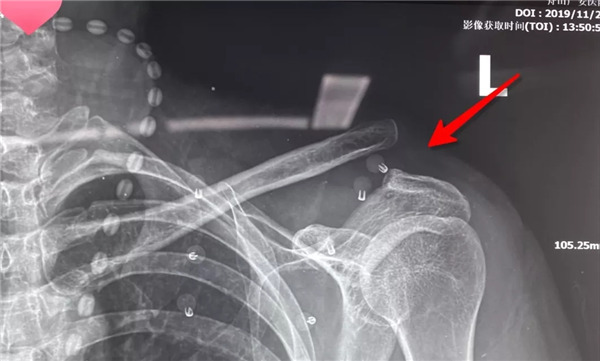

經(jīng)患者與家屬同意后,羅軍主任手術(shù)團隊成功為患者實施了左肩鎖關(guān)節(jié)復(fù)位Y型Endobutton固定系統(tǒng)固定術(shù)。手術(shù)只用50分鐘時間。術(shù)后X片復(fù)查顯示肩鎖關(guān)節(jié)脫位完全復(fù)位,術(shù)后第二天楊女士在康復(fù)醫(yī)師指導(dǎo)下開始進行左肩關(guān)節(jié)功能鍛煉,楊女士左肩部疼痛明顯減輕,左肩關(guān)節(jié)可抬起、前舉,功能較術(shù)前明顯改善,楊女士大約再經(jīng)過3-4周康復(fù)訓(xùn)練左肩關(guān)節(jié)功能可恢復(fù)正常。

術(shù)后拍片